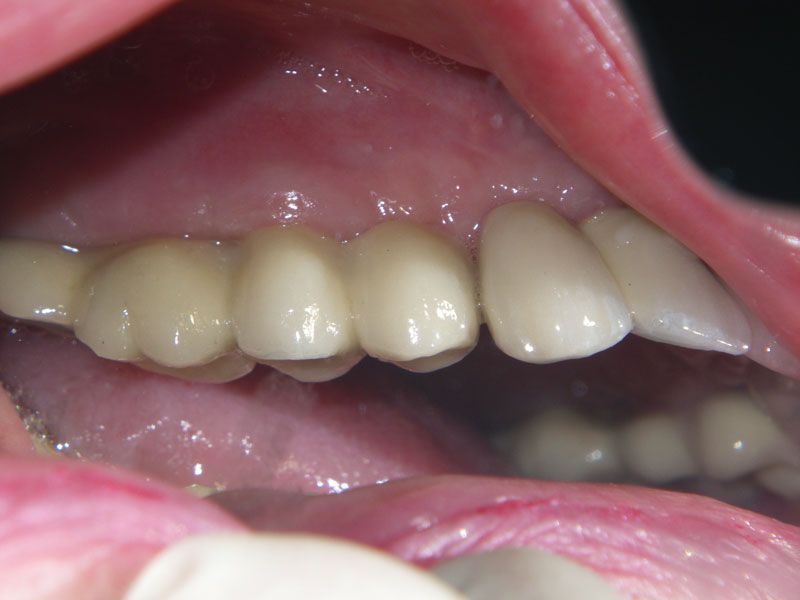

Протезирование было проведено с помощью трех мостовидных протезов, причем выбор цвета и формы зубов был предоставлен пациенту. Оказалось, что высоко-эстетичнын зубы, были мечтой пациентки всю жизнь. Они и были выбраны. Диссонанс с собственными зубами, которыми так дорожила наша пациентка до операции, оказался столь сильным, что теперь в планах пациентки заняться нижней челюстью в плане функционально-эстетическойй реабилитации фронтального участка несъемным протезированием на имплантах.